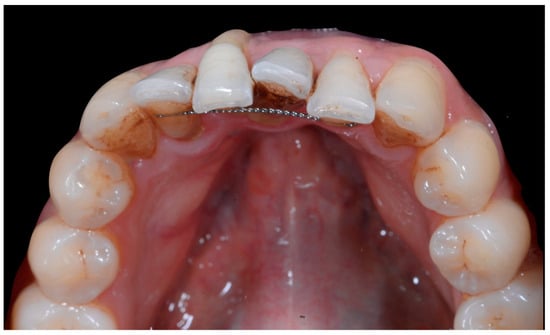

Occlusal views (Figure 4) confirmed the presence of a mandibular retainer which appears intact, without fracture or debonding, along its entire length. In addition, the vestibular surface of 41 appeared to have a difference in visibility from the adjacent teeth. Based on these clinical findings, wire syndrome starting on tooth 41, called the “X-effect” type, was suspected.

Figure 4.

Early wire syndrome. Occlusal view.

Although it is reasonable to assume that tissue damage occurs from the initiation of FS, clinical manifestations start to be visible when the disease process results in root displacement. We can therefore propose a clinical gradient with dental and periodontal consequences varying from a minor problem to the exposure of the root to the apex of the affected tooth (Figure 4). The three clinical situations described in this article illustrate the main stages of this gradient.